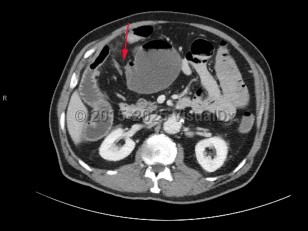

A small bowel obstruction (SBO) occurs when intraluminal bowel contents fail to pass through the small intestine. Impaired passage of bowel contents results in dilation of the proximal bowel, with fluid accumulation, gas production, increased intraluminal pressure, and bacterial overgrowth. This results in abdominal distension and pain, nausea, and vomiting, with risk of bowel ischemia and perforation.

- Ingestion of multiple magnets

SBOs can be classified as partial or complete. Partial SBOs permit some passage of bowel contents past the obstruction site, while complete SBOs are associated with the inability to pass any gas or fluid past the obstruction. Partial SBOs can further be stratified into high-grade or low-grade, depending on the severity of obstruction, with low-grade SBOs presenting with less severe symptoms. A simple SBO is characterized by a single point of obstruction. A closed-loop obstruction is characterized by occlusion of the bowel at 2 points and has the highest risk of ischemia due to occlusion of the blood supply.

Patients most commonly present with diffuse or periumbilical abdominal pain, often described as colicky, with paroxysms every few minutes. Pain may become localized or constant if the bowel becomes ischemic or perforated. Abdominal distension is highly suggestive, as is constipation. Patients commonly have nausea and vomiting, which varies in severity based on the location of the obstruction, with proximal SBOs presenting with more severe symptoms. Patients with complete obstructions stop passing stool or flatus, although this may be delayed for 12-24 hours as the bowel distal to the obstruction continues to pass contents. Rarely, patients may have intermittent obstruction, often partial and low-grade, with spontaneous resolution of symptoms between episodes.

The greatest concern from an SBO is the risk of increased dilation leading to necrosis and bowel perforation. Patients with bowel ischemia or perforation typically present with more severe signs and symptoms, often with evidence of peritonitis, sepsis, and hemodynamic instability.